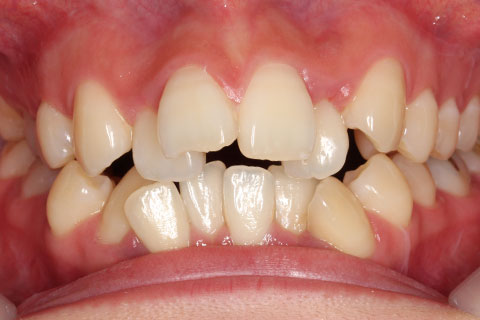

ハーフリンガル矯正3:上の歯のみ舌側矯正で治療(矯正期間24ヶ月)

治療前

治療中(開始直後)

治療中(開始半年後)

治療後

- 年齢・性別

- 25歳女性

- 治療期間

- 2年0ヶ月

- 抜歯

- 上下4番抜歯

- 治療費

- 110万円

- 治療内容

- 施術の副作用(リスク)

- 表側矯正と比較して、力学的な操作性が複雑なため、ボーイングエフェクトを起こしやすい。